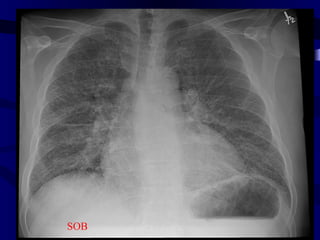

pulmedema

SOB